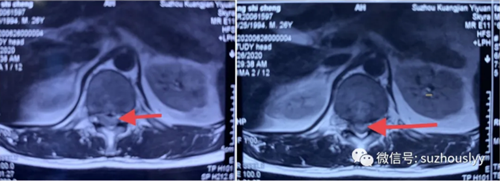

患者,男,25岁,打篮球时向前俯冲摔倒,导致脊柱过伸性损伤,伤后顿时感腰部疼痛,双侧臀部及双下肢疼痛麻木,一过性双下肢无力,短暂平卧休息后送入当地医院治疗,行腰椎正侧位片、CT、MRI提示:胸12腰1间隙椎间盘组织突入椎管,脊髓明显受压。

后经朋友介绍,来到我院骨二科就诊,主任医师李国强接诊后带领团队,通过询问病史、体格检查及阅片,对患者的病情做了细致的分析研讨,确认胸12腰1为责任间隙,此次外伤导致出现神经症状,因脊髓神经根受压明显,并制定了一套安全有效、风险可控的最佳治疗方案。在麻醉科的配合下李主任带领团队医师为患者局部强化麻醉下行胸12腰1椎间盘突出症脊柱内镜下髓核摘除脊髓神经根减压术,手术非常顺利,术后患者双侧臀部及下肢疼痛麻木症状消失,而且腿脚也灵活了,第二天他就能下地行走,像正常人一样自然平稳。